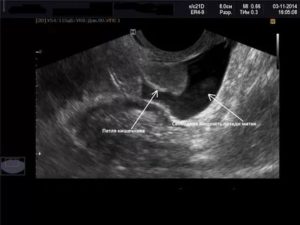

Если проведено УЗИ пациентке детородного возраста, и в малом тазу обнаружена свободная жидкость, а также выявлено вне матки плодное яйцо в окружении кровяных сгустков, скорее всего, врач диагностирует внематочную беременность. Скопление воды вызывают и другие причины, в частности, это болезни различных органов брюшной полости, например, подобная симптоматика может сопровождать болезни печени.

Позадиматочное пространство находится за маткой, ограничивается оно брюшиной. Зачастую жидкость скапливается в нижней части. У здоровых женщин явление вызвано естественными причинами, однако порой имеют место быть серьезные проблемы.

Этот показатель определяется на УЗИ. В полость вводится специальный датчик, благодаря которому на экране отображаются все внутренние органы. Врач может оценить строение матки, посмотреть размеры яичников. Если вещество отсутствует, то оно не визуализируется.

Достаточно часто свободная жидкость за маткой является признаком патологии внутренних органов женщины. Определить на УЗИ точный объем такого образования крайне сложно, потому что она растекается между репродуктивными органами. Медики разработали определенные критерии, позволяющие оценить состояние жидкости в позадиматочном пространстве (измеряется длина вертикального уровня образования):